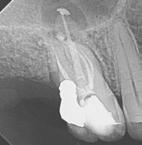

Clinical case performed by Dr. Benedict Bachstein (Figures 1-3)

The patient was diagnosed with irreversible pulpitis in tooth number 14, which presented multiple canals with highly complex anatomies. All canals were instrumented to 25/.04 and cleaned with Odne®Clean following the recommended clinical protocol. The use of Odne®Clean enabled the identification of five canal orifices and clearing of apical deltas.

Clinical case performed by Dr. Brett Gilbert (Figures 4 and 5)

In this case, Dr. Gilbert was initially unable to locate the MB2 canal, despite thorough attempts using ultrasonic and a microscope. After performing the irrigation protocol with Odne®Clean, the MB2 became visible. Following activation, the filling material extended completely through the MB2.

Clinical case performed by Dr. Sameer Jain (Figures 6 and 7)

The RCT involved a deep split tri-furcated premolar. Use of Odne®Clean enabled access to the advanced canal anatomy.